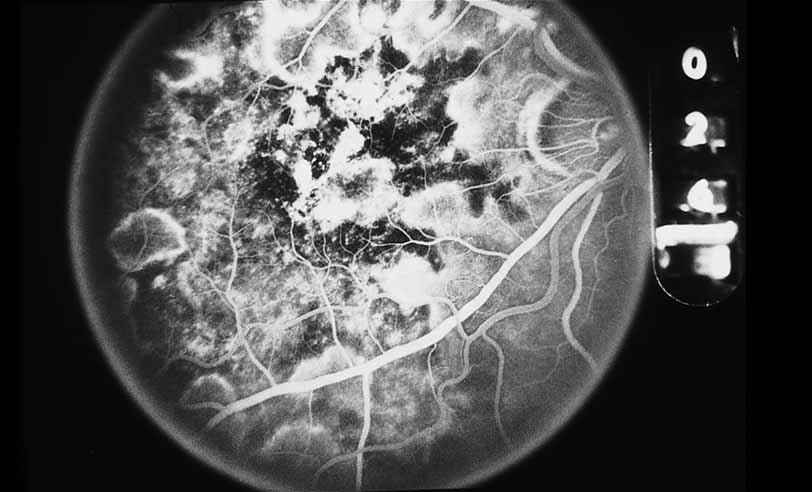

A third instance in which fluorescein angiography concentrating on the optic nerve may be helpful is in eyes with vascular engorgement of the optic nerve, especially with media opacities. Fluorescein angiography may help the clinician distinguish abnormally leaking capillaries from neovascularization. In acute multifocal hemorrhagic retinal vasculitis, optic nerve involvement is common in the early stages of the disease, 47 with optic nerve disc neovascularization seen later (see Figs. 10, 11, 12, and 13). Another fluorescein angiographic clue to the distinction between optic disc vessel engorgement and true neovascularization is the presence of associated large zones of retinal capillary nonperfusion such as those seen in sarcoidosis (see Figs. 14 and 15),34–40 acute multifocal hemorrhagic retinal vasculitis (see Figs. 10 and 11),47 or Eale disease (see Figs. 16 and 17).48–52

Fig. 12 Acute multifocal hemorrhagic retinal vasculitis. The patient later developed disk neovascularization with vitreous hemorrhage. Note the areas of neovascular leakage from the optic nerve.